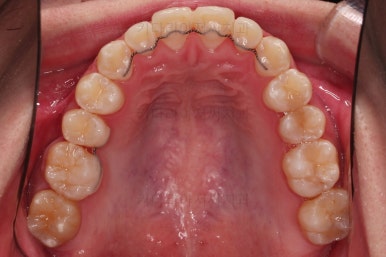

이제 전후 비교를 해볼게요.

1년 7개월 만에 매우 고난이도의 치료를 임플란트 없이 사랑니까지 당겨와서 사용한 만족스러운 치료였습니다.